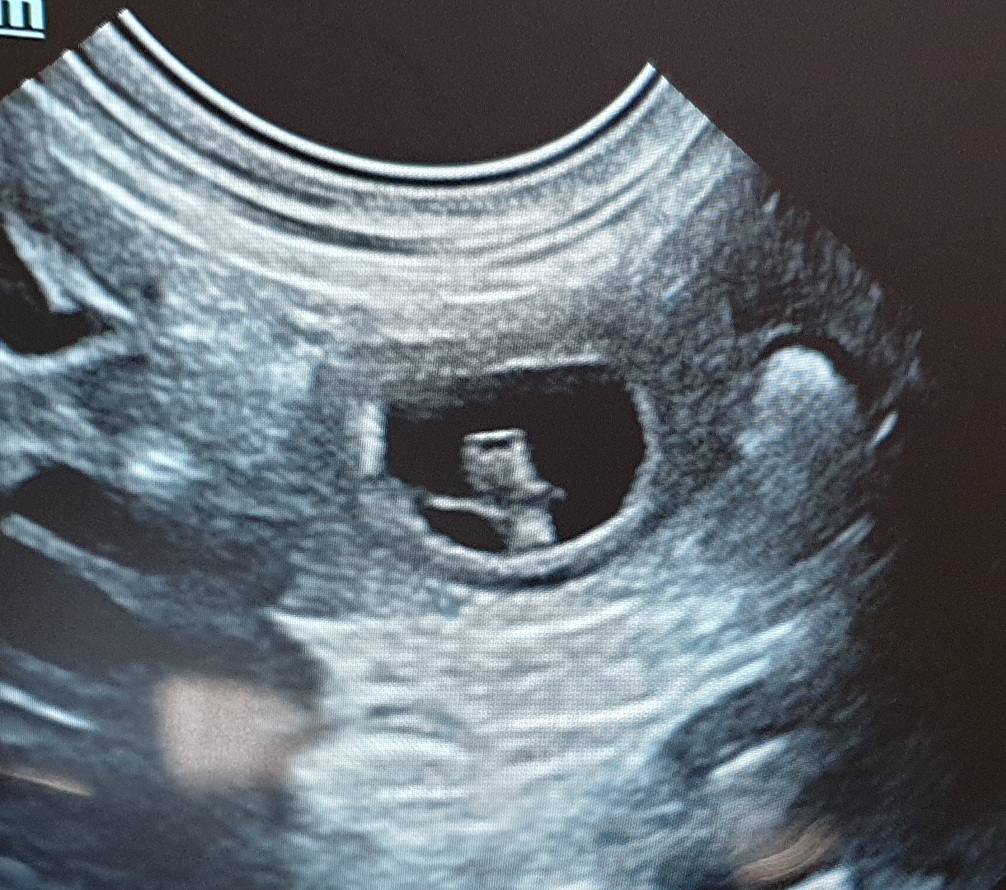

Aslana spielt wieder gerne, frisst aber immer noch sehr mäkelig. Ihr Gewicht ist ebenfalls unverändert. Und nun ist auch der Ultraschall dran:

Aslana ist wieder trächtig! Gezählt habe ich 6-7 Welpen, das lässt sich aber im Ultraschall nicht genau sagen, weil man nicht alle Welpen auf ein Bild bekommt. Wir freuen uns auf die kommenden Wochen :o).